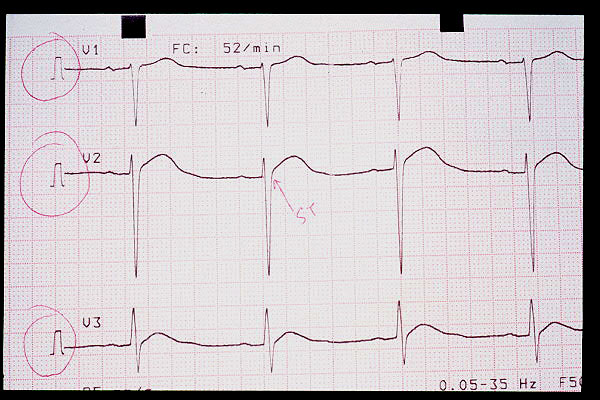

Elevación de ST en V2, bloqueo AV 1º (mV en 5 mm)